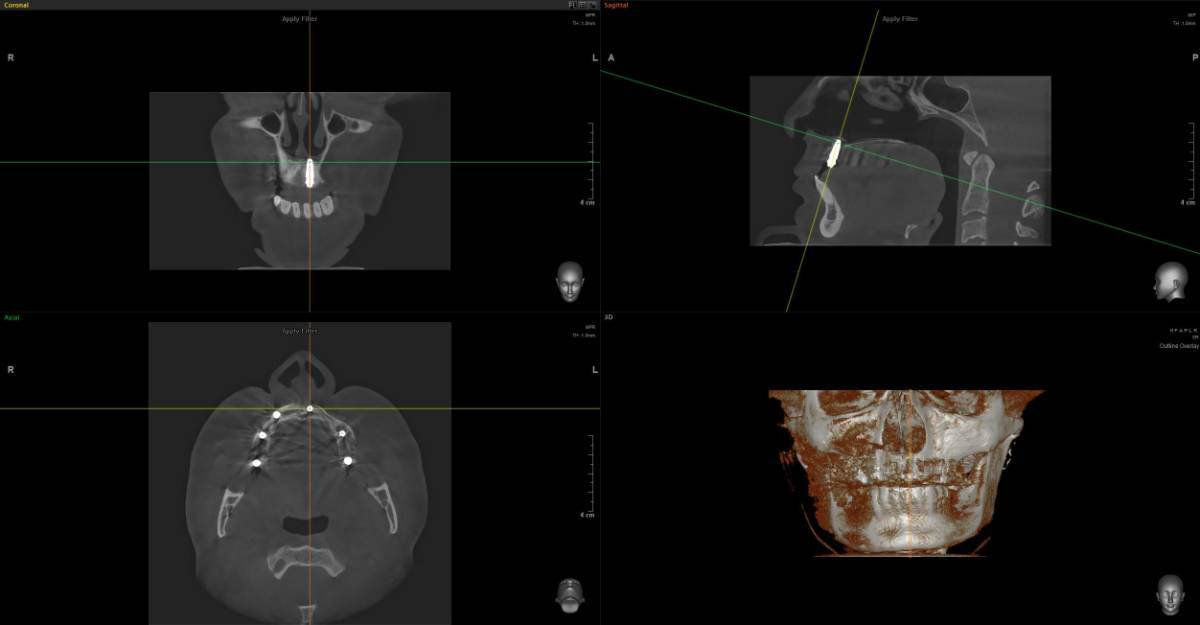

Добрый день, пожалуйста объясните что с зубом простыми словами, я если честно ничего не понял, там проблемы? Просто к стоматологу пойду через неделю только чтобы мне объяснили КТ, хочется сейчас узнать хоть что-то: 16 зуб эндодонтически лечен. Коронковая часть восстановлена рентгеноконтрастным материалом. Небный корень: канал широкий, обтурирован высококонтрастным материалом, верхушка корня не закрыта. Периапикально очаг деструкции костной ткани 4,5х4мм. запломбирован. Щёчно-медиальный корень – признаки дилацерации корня, канал запломбирован частично. Периапикально очаг деструкции 4х4мм Щёчно-дистальный корень: длина корня не более 4мм, в канале и за верхушкой корня определяется пломбировочный материал. Периапикально признаки деструкции костной ткани, очаг с нечеткими контурами. Жалоб на зуб вроде нет.. просто если очень долго вообще не жевать ничего или вообще челюстью не работать, при надкусывании чувствуется дискомфорт, но очень очень быстро проходит и больше не появляется